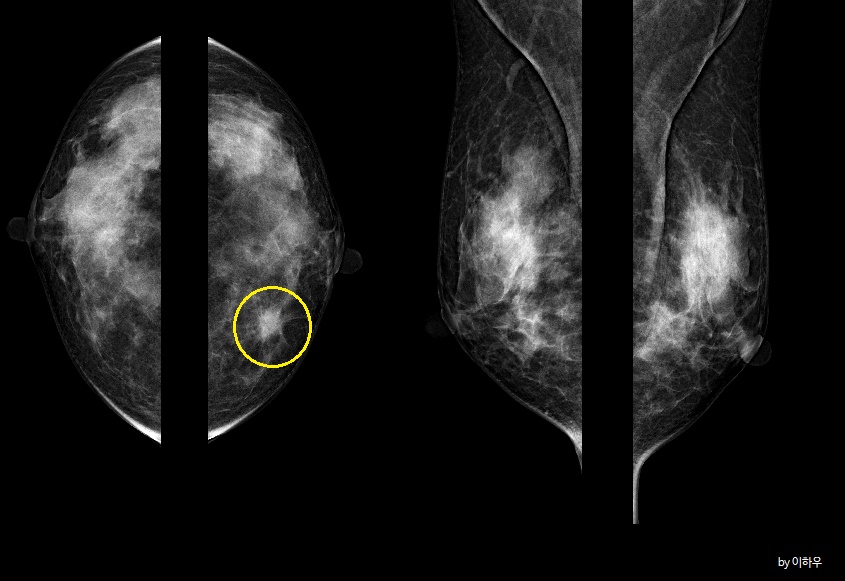

3. 구조적 왜곡이라고 말하는 경우가 있습니다. 구조적 왜곡은 말이 조금 어려운데, 국소적으로 유방의 일부 부위에서 별이 모양이나 혹은 그물 모양으로 뻗어나가는 듯한 부분이 보이게 되면 그 부분의 구조가 왜곡, 즉 뒤틀려 있다고 하게 되고 질병의 유무를 확인하게 됩니다.

4. 국소적 비대칭 음영이 보인다고 표현하는 경우가 있습니다. 이런 경우는 위의 2번과는 달리 유방 촬영 면 2곳에서 모두 보이는 경우를 말하는데, 이 부분이 정말로 어떤 혹인지는 알 수가 없어 이렇게 표현합니다.